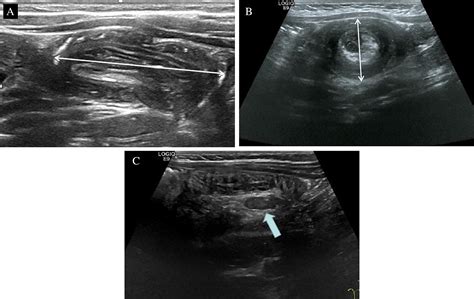

When performing an ultrasound to detect intussusception on ultrasound, radiologists look for specific signs that indicate the presence of intussusception. These signs include:

• Target or doughnut sign: This appears as concentric rings of alternating hypoechoic and hyperechoic layers, representing the invaginated intestine.

• Pseudo-kidney sign: This sign is seen when the intussusceptum (the invaginated segment) appears as a hypoechoic mass with a hyperechoic rim, resembling a kidney.

• Crescent-in-doughnut sign: This sign is observed when there is a crescent-shaped hypoechoic area within the doughnut sign, indicating the presence of mesenteric fat.